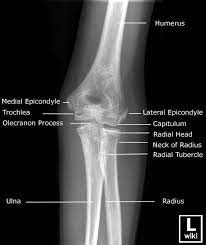

A patient's guide to elbow anatomy. Normal radiographic anatomy of the elbow | radiology case human anatomy and physiology. To install xray anatomy on your windows pc or mac computer, you will need to download and install the windows pc app for free from this post.

There is a printable worksheet available for download here so you can take the quiz with. Radiology imaging anatomy for radiology student and tech / technologist ( xray ct mri ). It contains information about the normal anatomy and the most common pathology. Documents similar to common errors in xray interpretation 2.